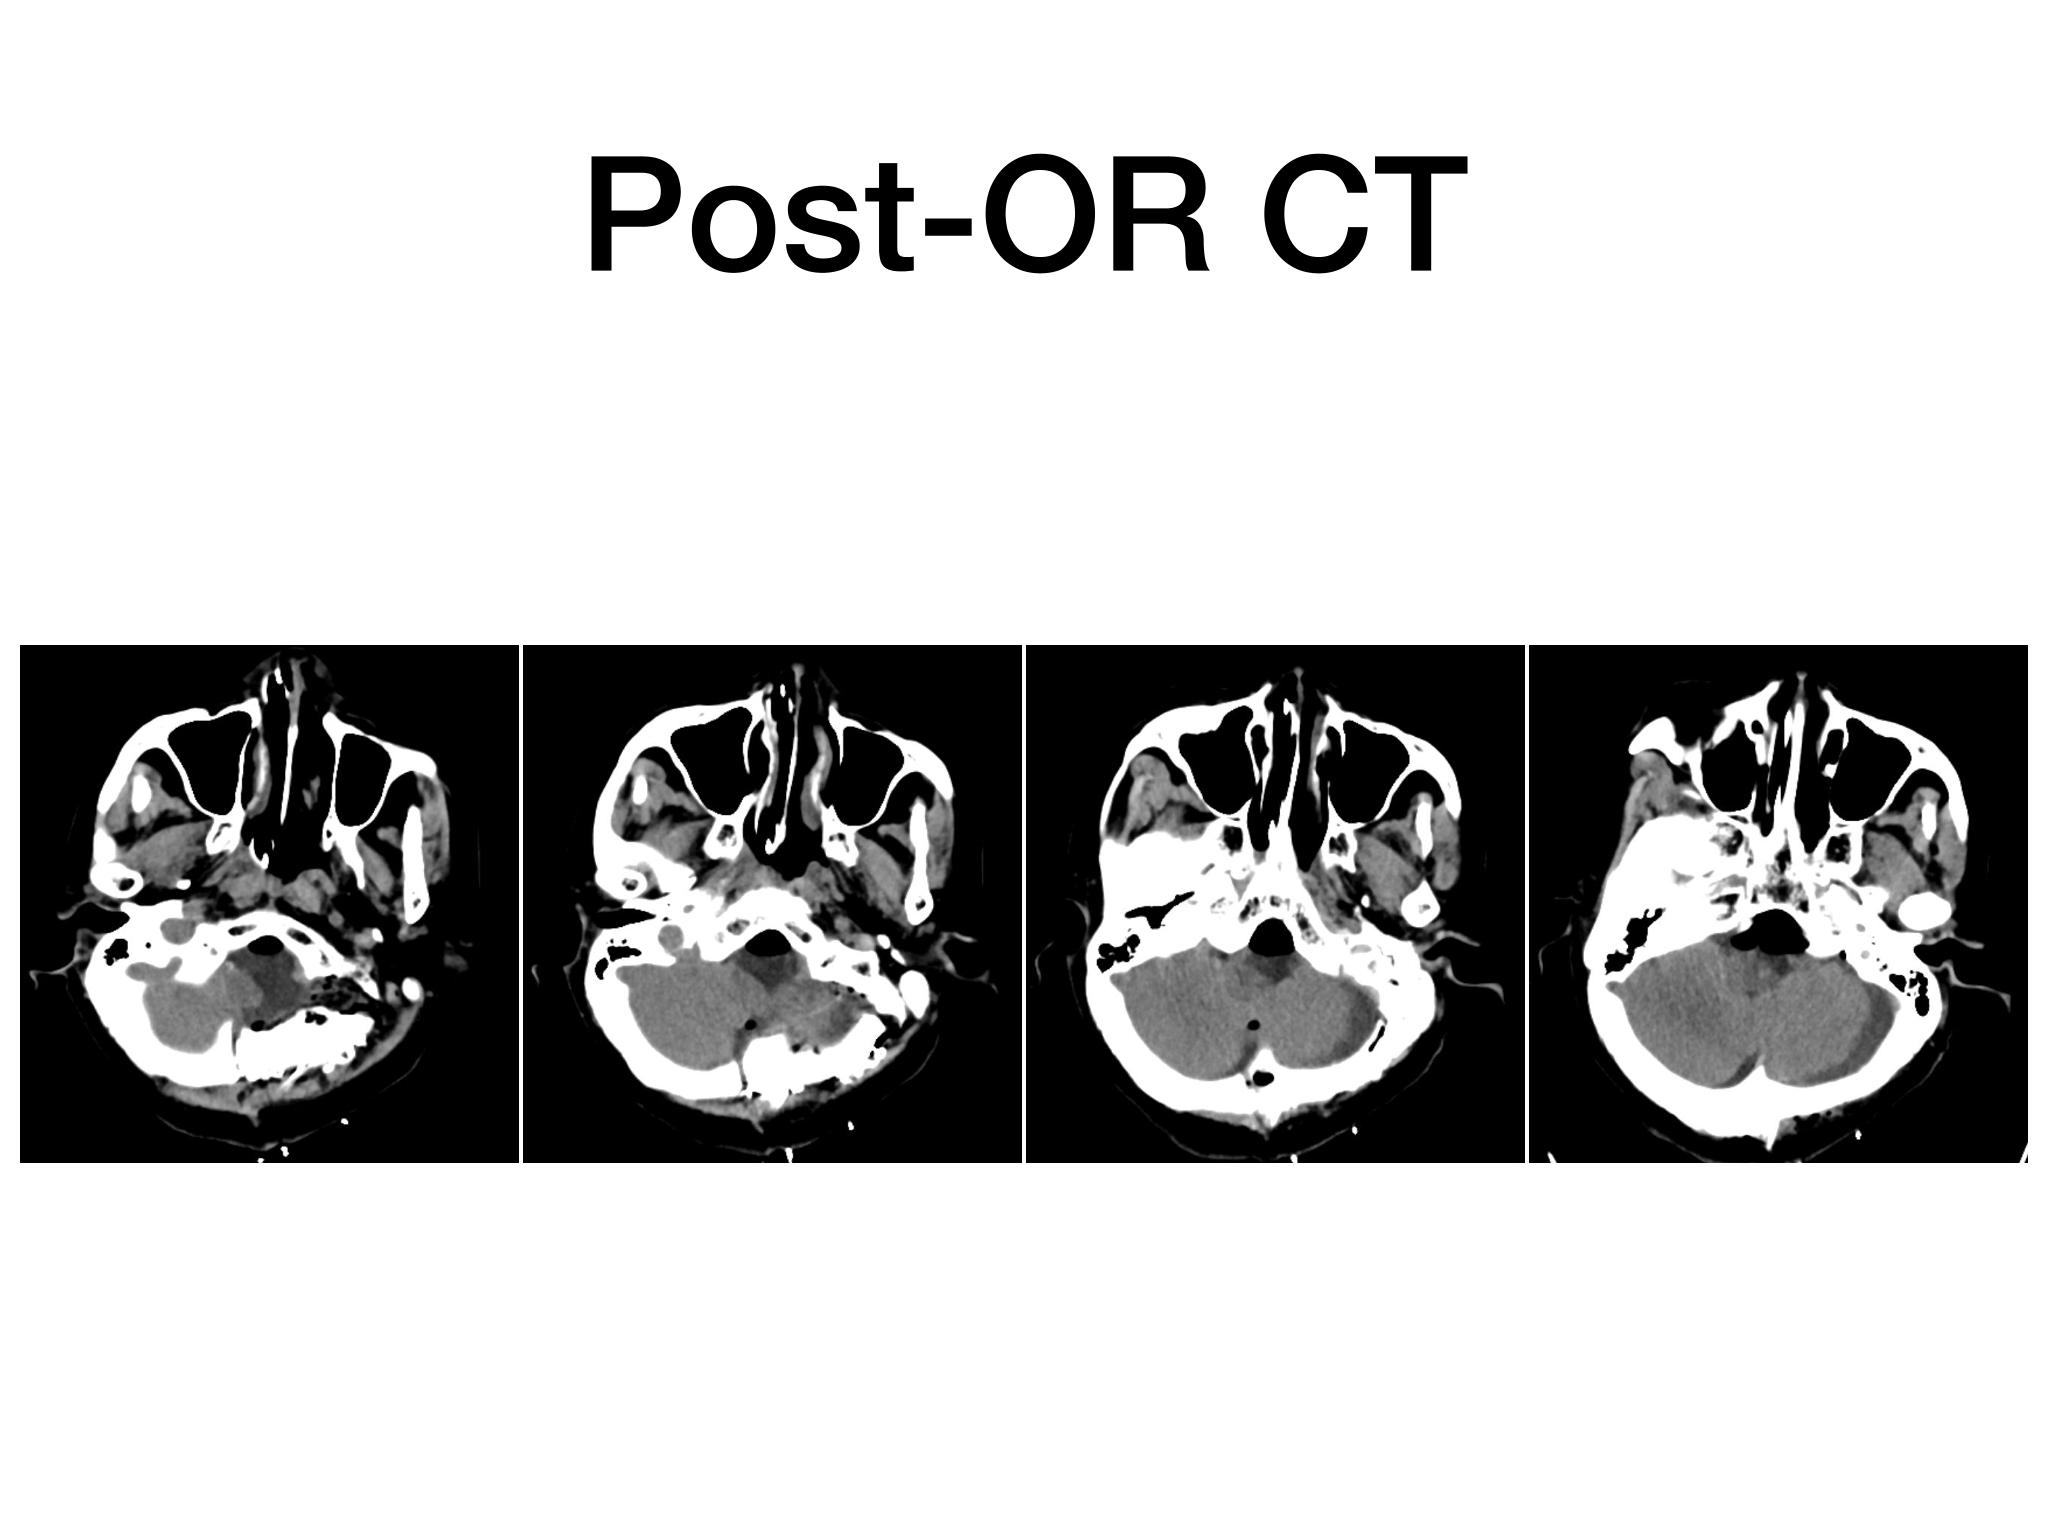

汇报一例后颅底肿瘤手术。为枕骨大孔巨大腹侧型脑膜瘤,该患者高龄,同时合并肺Ca,术前2周急性加重,枕骨大孔疝前期表现,术前已有延髓压迫及后组颅神经麻痹表现。经详细评估后采用远外侧经髁窝入路,最大化显露,重点保护延髓、后组颅神经,尽可能“零骚扰”。术中肿瘤质地韧,血供一般,与肿瘤上极与后组颅神经黏连紧密,最终99%切除,残留约1%,术后顺利康复出院,无新发症状,为后续进行肺部病变化疗创造有利条件。